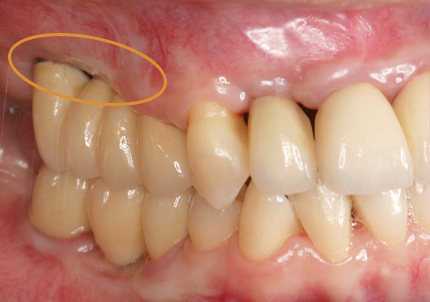

1.初診時口腔内(2007年7月31日)

主訴 ①:左下痛くて歯肉が腫れる

左下7番部ポケット7~9ミリ

左下5番部ポケット3~5ミリ

治療計画 ①:歯周病初期治療、歯周外科